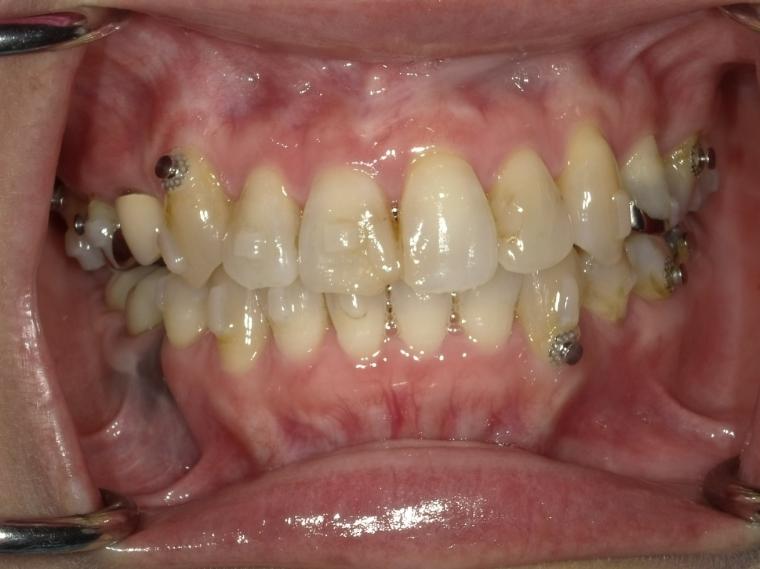

AFTER

右下第二大臼歯は欠損していたため、マウスピース矯正で歯列を整えてから、インプラントを1本埋入しました。

現在も定期健診で拝見させていただいています。